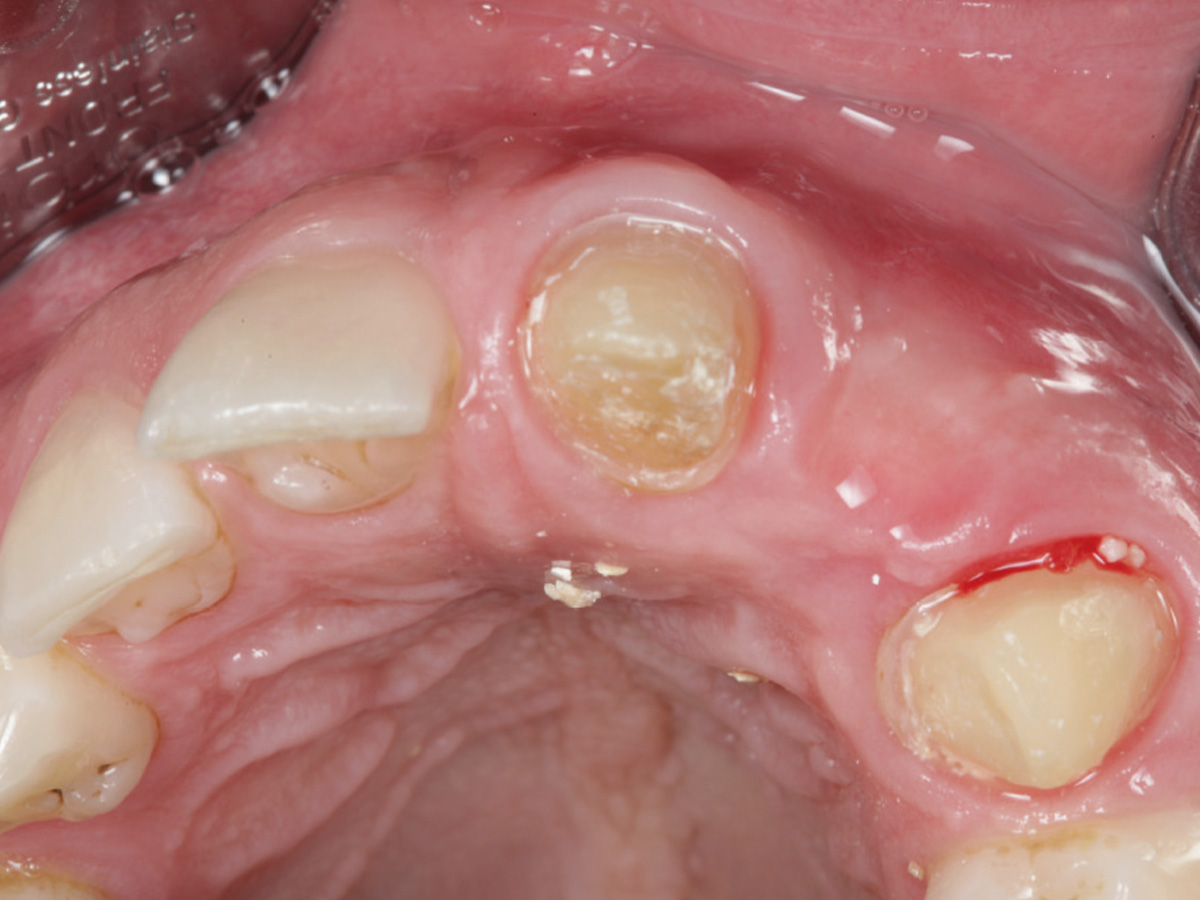

Abbildung 8

6 Monate nach der Augmentation.